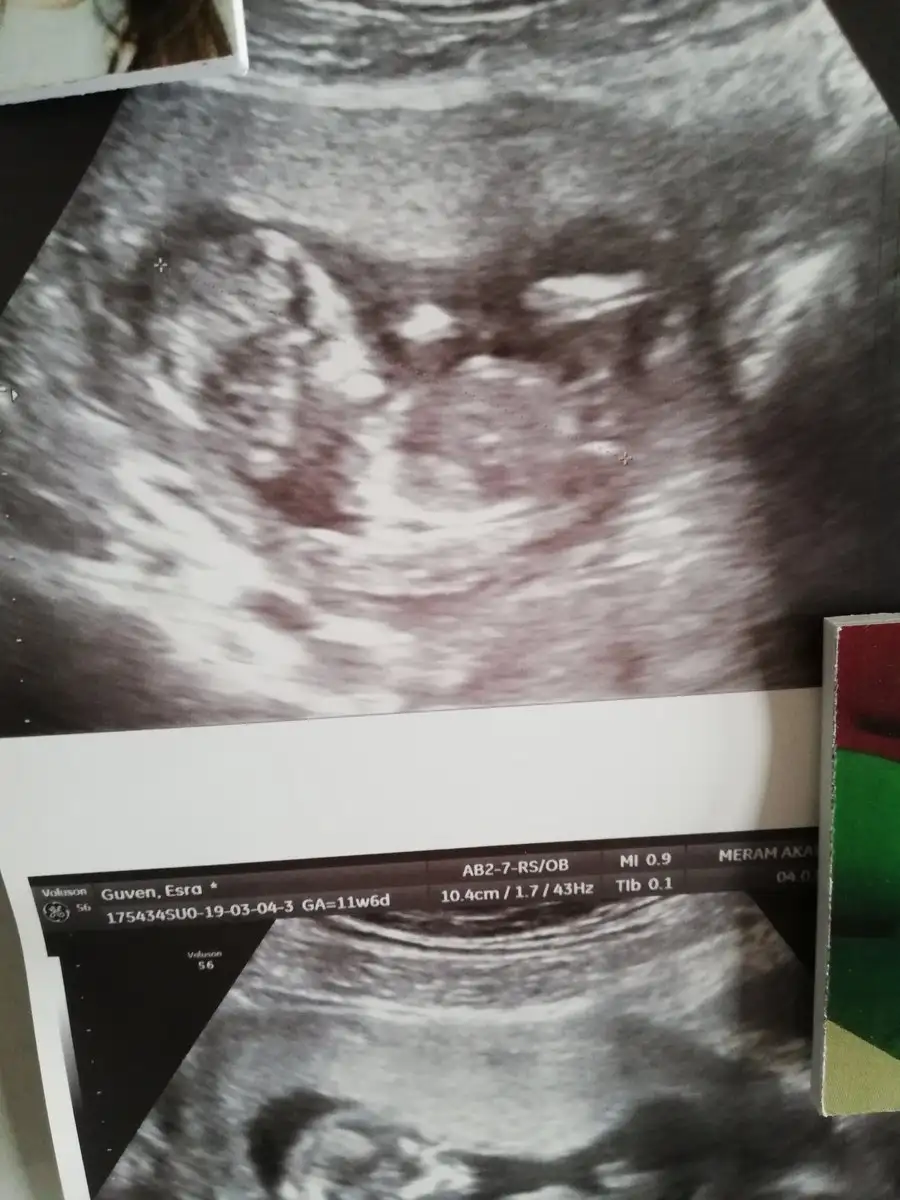

Teyzeleri geldik biiizzz. %100 erkek dedi, ense kalınlığı 1.4 cm cıktı. 5 gün önden gidiyormuş herşey yolunda dedi doktor şükür. Darısı ogrenmeyenlerin başına

Ooh gözün aydın hadi oğlan anası oldun demek :))) yalnız enseleri bile aynı bizimkilerin benim de 1.4 tü yavrumun :) bakalım benimkinin cinsiyeti ne olacak. Bende yüksek ihtimal erkek diye düşünüyorum ama bakalım :) gözün aydın Rabbim sağlıklı kucağına almayi da göstersin